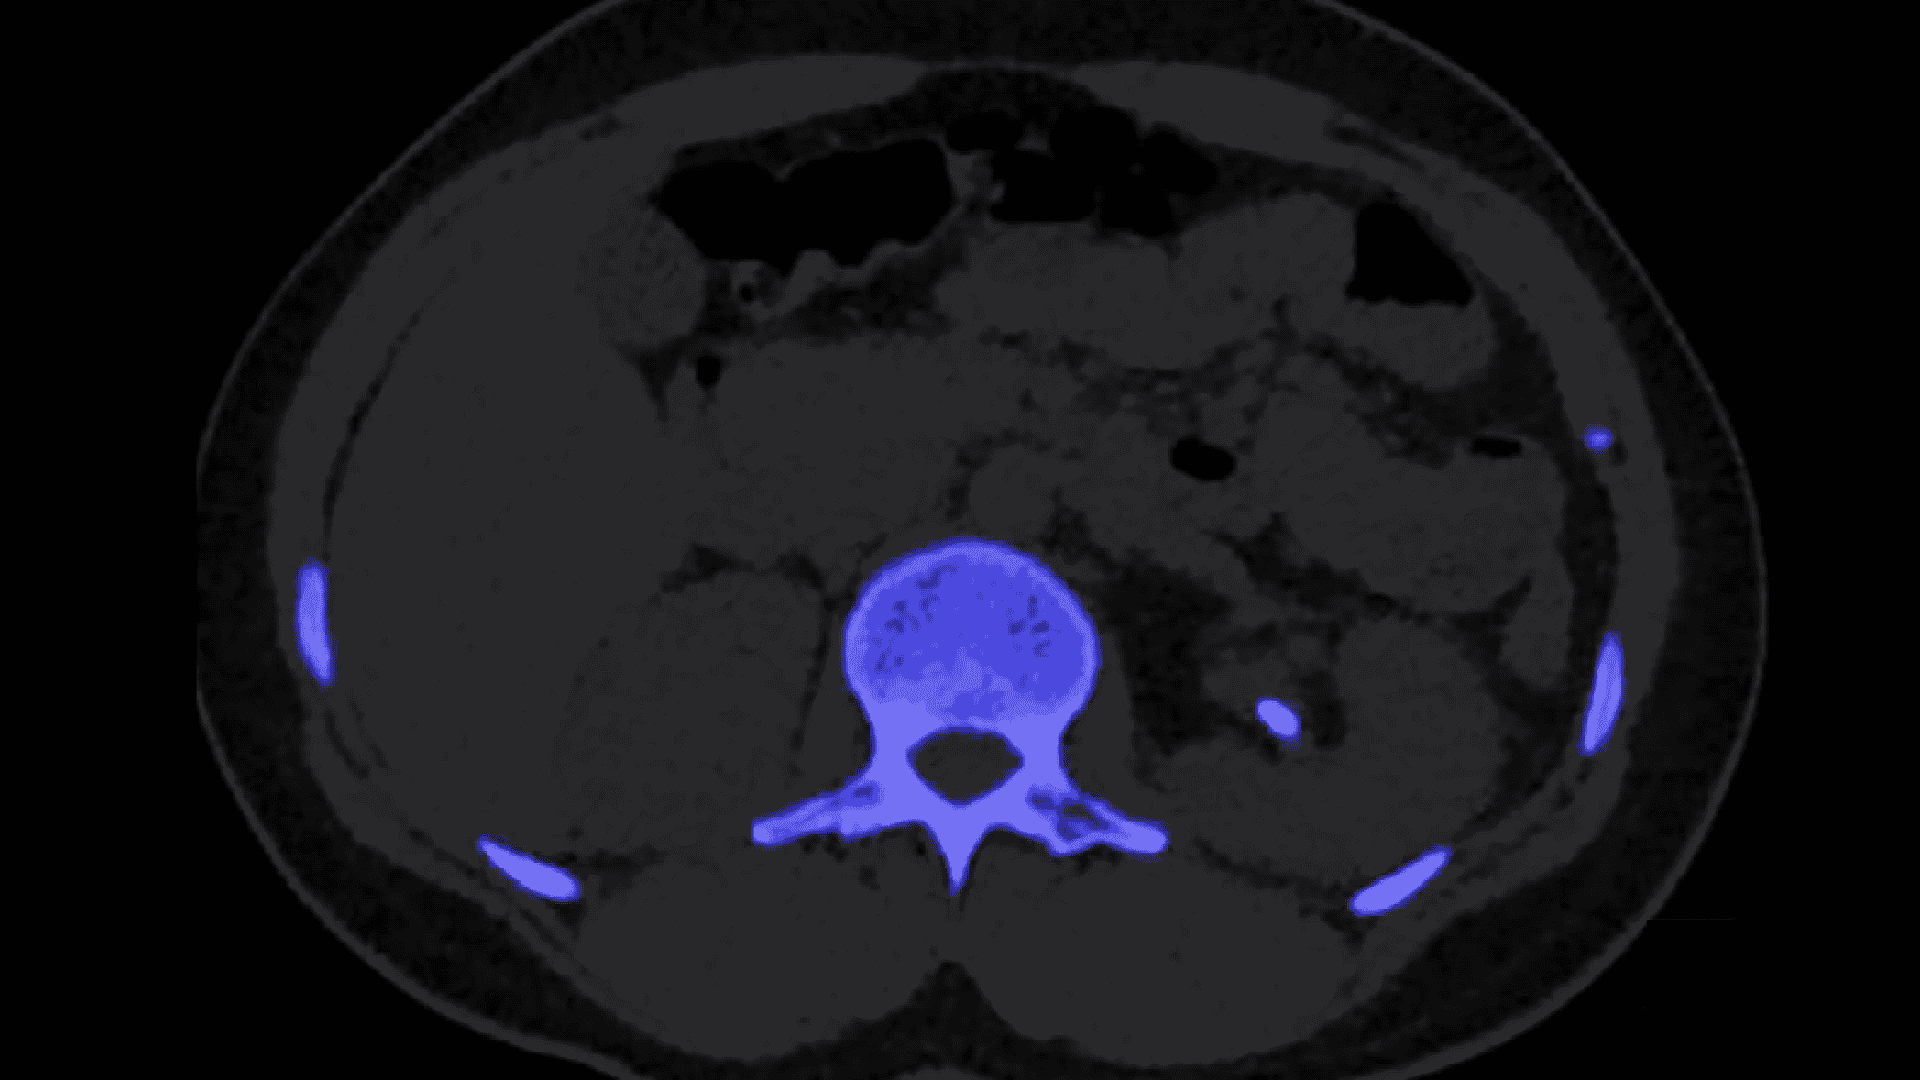

Vascularización tiroidea normal en Doppler color. Este patrón basal, con flujo conservado y velocidades picosistólicas de 20–40 cm/s, es la referencia indispensable para distinguir hiperfunción, inflamación y autoinmunidad en la patología tiroidea difusa.